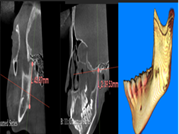

A través de los cortes tomográficos (Figura 3) se pudo observar que la rama mandibular derecha medía 43.85 mm y la izquierda 39.53 mm dando una diferencia de 4.34 mm lo que evidencia que la asimetría que presenta la paciente es a causa de la discrepancia de tamaño de las ramas mandibulares (A).

En el corte a nivel de la articulación temporomandibular izquierda se observó un aplanamiento del cóndilo con áreas de cambios osteoartríticos leves (B); en la articulación temporomandibular derecha el cóndilo se encuentra con una severa osteoartritis que muestra una imagen hipodensa a nivel condilar compatible con un quiste subcondral (C).

Diagnóstico de ATM: La paciente presenta una displasia discal sin reducción bilateral.

Plan de tratamiento: Debido a todo lo expuesto se decidió colocar un aparato de avance mandibular tipo monoblock para recapturar el disco. Para ello se inició con la realización de una mordida constructiva para la confección del aparato, se llevó a una coincidencia de las líneas media y un adelantamiento mandibular de 3 mm (Figuras D, E y F). Posteriormente se envió los registros para la confección del dispositivo de avance mandibular tipo monoblock (Klammt Clase II) que fue instalado en marzo del 2023 constatando de que se encuentre totalmente adaptado (G), las indicaciones de uso fueron más de 20 horas al día aconsejando que la paciente se lo retire únicamente para comer y para el aseo respectivo. Los controles se realizaron a las 2 semanas y después con una frecuencia mensual durante 12 meses.